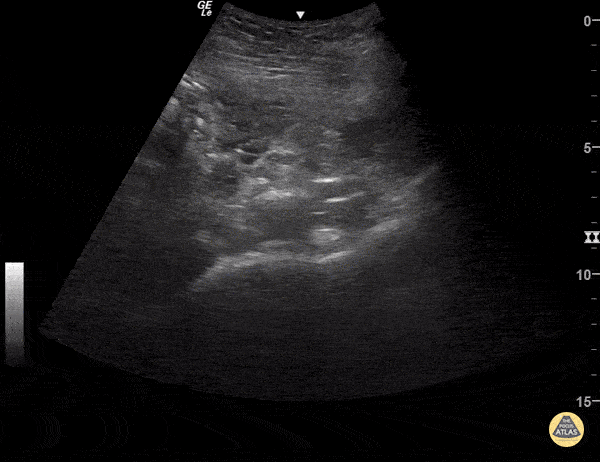

IUP with hemorrhagic cyst and subchorionic hemorrhage. Sukh Singh, MD